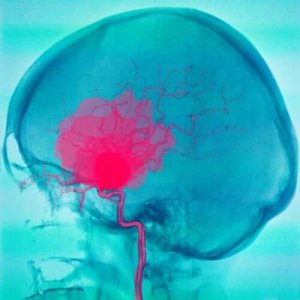

くも膜下出血

くも膜下出血は、くも膜と軟膜の間に動脈からの血液が溜まる状態で、その原因はさまざまです。

最も一般的なのは、動脈瘤の破裂ですが、他の原因もあります。

これらの髄膜が壊れると、出血が始まります。これらは40〜60歳の間に発生するのが一般的で、次のような症状を発症します。